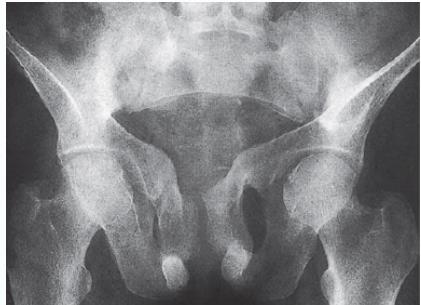

- Trefoil pelvis – acetabular protrusion

- Neck of femur

- Pubic bones